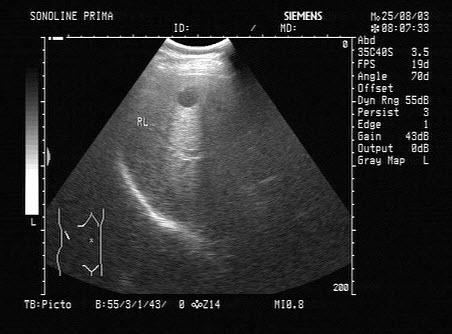

某患者左肾超声声像图如下,最可能的诊断为()

根据超声图像所示,该病例为哪型肾积水()